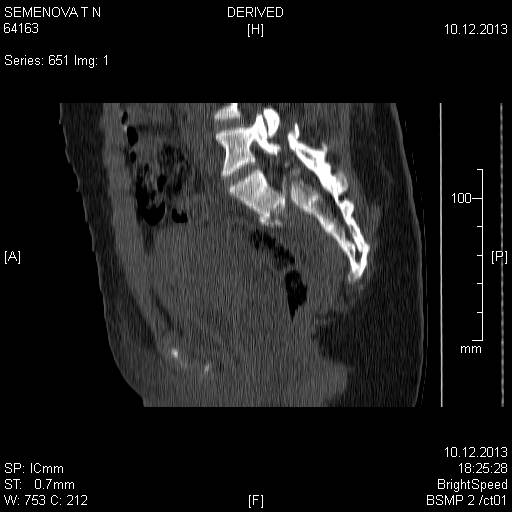

Доброго времени суток коллеги! Прошу вас подсказать тактику в решении оперативного лечения следующего сложного повреждения таза. Был ли опыт в фиксации подобных повреждений? Травма 03.12.2013,больная переведена из лечебного учреждения соседней области.На данный момент у больной следующий диагноз: ЗЧМТ,сотрясение головного мозга;Закр. травма грудной клетки,множественные переломы ребер справа с повреждением ткани легкого,правосторонний гемопневмоторакс,состояние после торакоцентеза;Закр.травма живота,разрыв селезенки,гемоперионеум, состояние после лапаротомиии спленэктомии;Закр. оскольчатый перелом сред-верх\3 левой бедренной кости, состояние после накостного металлостеосинтеза; Закр.поперечный переломовывих на уровне S1S2, многооскольчатый перелом латеральных масс крестца с обеих сторон,перелом обеих лонных и седалищных костей. Перелом поперечных отростков L1,L2,L3,L4, L5 позвонка. ШОК 3ст. Вкратце изложил диагноз. В настоящее время состояние больной тяжелое. Первым этапом планируем наложить АНФ (переднюю раму) После стабилизации состояния необходимо будет выполнить фиксацию: . Имеется один вопрос - какие импланты необходимы т.е. в какой комбинации и какая последовательность фиксации?

Добрый день! Станислав! Повреждение таза действительно тяжелое. В данном случае по мимо перелома передних колонн, что не самое страшное, имеется H-образный перелом крестца со смещением каудальной части. перелом поперечных отростков подтверждает вертикально нестабильный характер травмы таза. Предложенная конструкция действительно является вариантом решения проблемы,а скомпоновать ее можно из любого транспедикулярного фиксатора той фирмы которая работает у вас с нейрохирургами.Но помимо этого необходимо выполнить декомпрессию корешков конского хвоста. в противном случае та неврология которая есть и сейчас останется на всю жизнь. Судя по тяжести состояния к лечению перелома крестца сможете приступить не скоро, скорее всего на данный момент доминирует легочный дисстресс синдром, наверняка есть анемия после гемопневмоторакса, лапаротомии и накостного остеосинтеза бедренной кости.Поэтому когда дойдет дело до крестца репонировать отломки будет весьма сложно. Мы бы начали с остеосинтеза ребер, чтобы сделать пациента мобильным, передние колонны можно фиксировать перкутанно винтами, сзади кроме илиолюмбальной конструкции, ляминэктомия с целью декомпрессии, репозиция и дополнительная фиксация реконструктивными пластинами, лучше LCP. Пригласите на операцию нейрохирурга-вертебролога. Успехов.

В данном случае кроме фиксации крестца требуется декомпрессия канала. А вправленный вывих надо удержать, и вертикальные пластины с юникортикальной возможностью в 2.7 мм помогут создать стабильность. Кроме этого, надо создать условия по предупреждению компрессии крестца с двух сторон. В связи с тем, что процедура заканчивается в области крестца, а также наличие повреждения позвонков, это ограничивает возможности педикулярной фиксации. Мне кажется, от боковой компрессии лучше удержала бы согнутая по контуру крыла узкая в 4.5 мм балка-пластина.